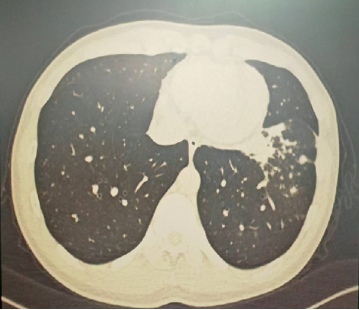

明确诊断后我们给予了正规治疗,患者咳嗽症状迅速缓解,1月后复查胸部CT提示肺部病变大部分吸收。

4月后再次复查胸部CT,提示病灶已经完全吸收。